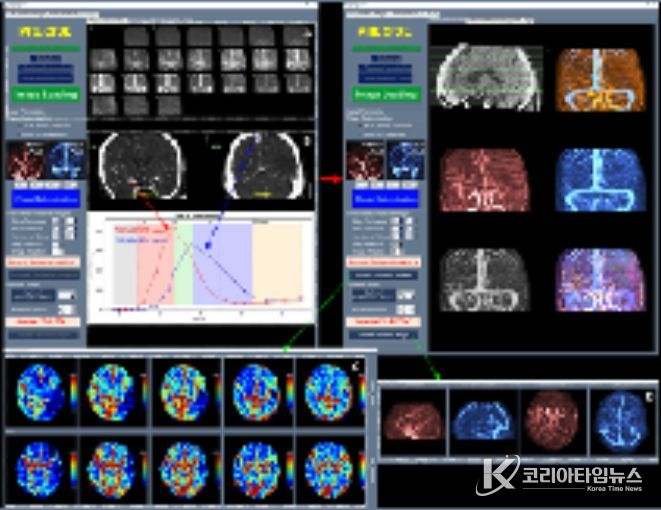

이와 함께 허혈성 뇌혈관 질환 환자를 대상으로 혈관재개통 치료가 필요한 환자 선별을 지원하는 소프트웨어 등 다양한 진단·치료 보조 AI 의료기기들이 혁신의료기기로 지정됐다.